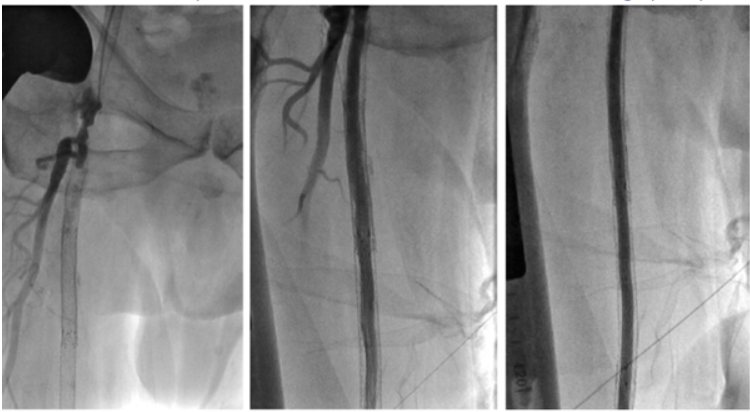

面对这两块 “硬骨头”,兴安盟人民医院心脏血管外科团队拿出了 “秘密武器”——(Jetstream 斑块旋切)高速旋切系统。这项技术到底有多厉害?打个比方:传统手术像 “撑气球”(用球囊撑开血管),但遇到钙化斑块就像 “石头堆里撑气球”,容易破,还得放支架 “撑住” 血管;(Jetstream 斑块旋切)就像迷你 “粉碎机”:医生通过大腿根一个针眼大的伤口(2-3 毫米),把一根细管子伸到血管里,管子前端的 “旋转刀头” 以每分钟 2 万转的速度,把钙化斑块磨成粉末,同时像 “吸尘器” 一样把碎屑吸走,血管瞬间 “通开”,还不用留支架!

高大叔手术中,医生 “听着声音” 切斑块:刀头碰到硬邦邦的钙化斑块,会发出 “滋滋” 的尖锐声;遇到软斑块,声音就变柔和,精准得像 “血管里的调音师”。

鞠大叔手术更为惊险:血管里的旧支架已经 “生锈”(内膜增生),刀头贴着支架内壁把增生组织一点点磨掉,全程没伤着血管,最后连保护伞里都吸出了一堆 “小碎石”!